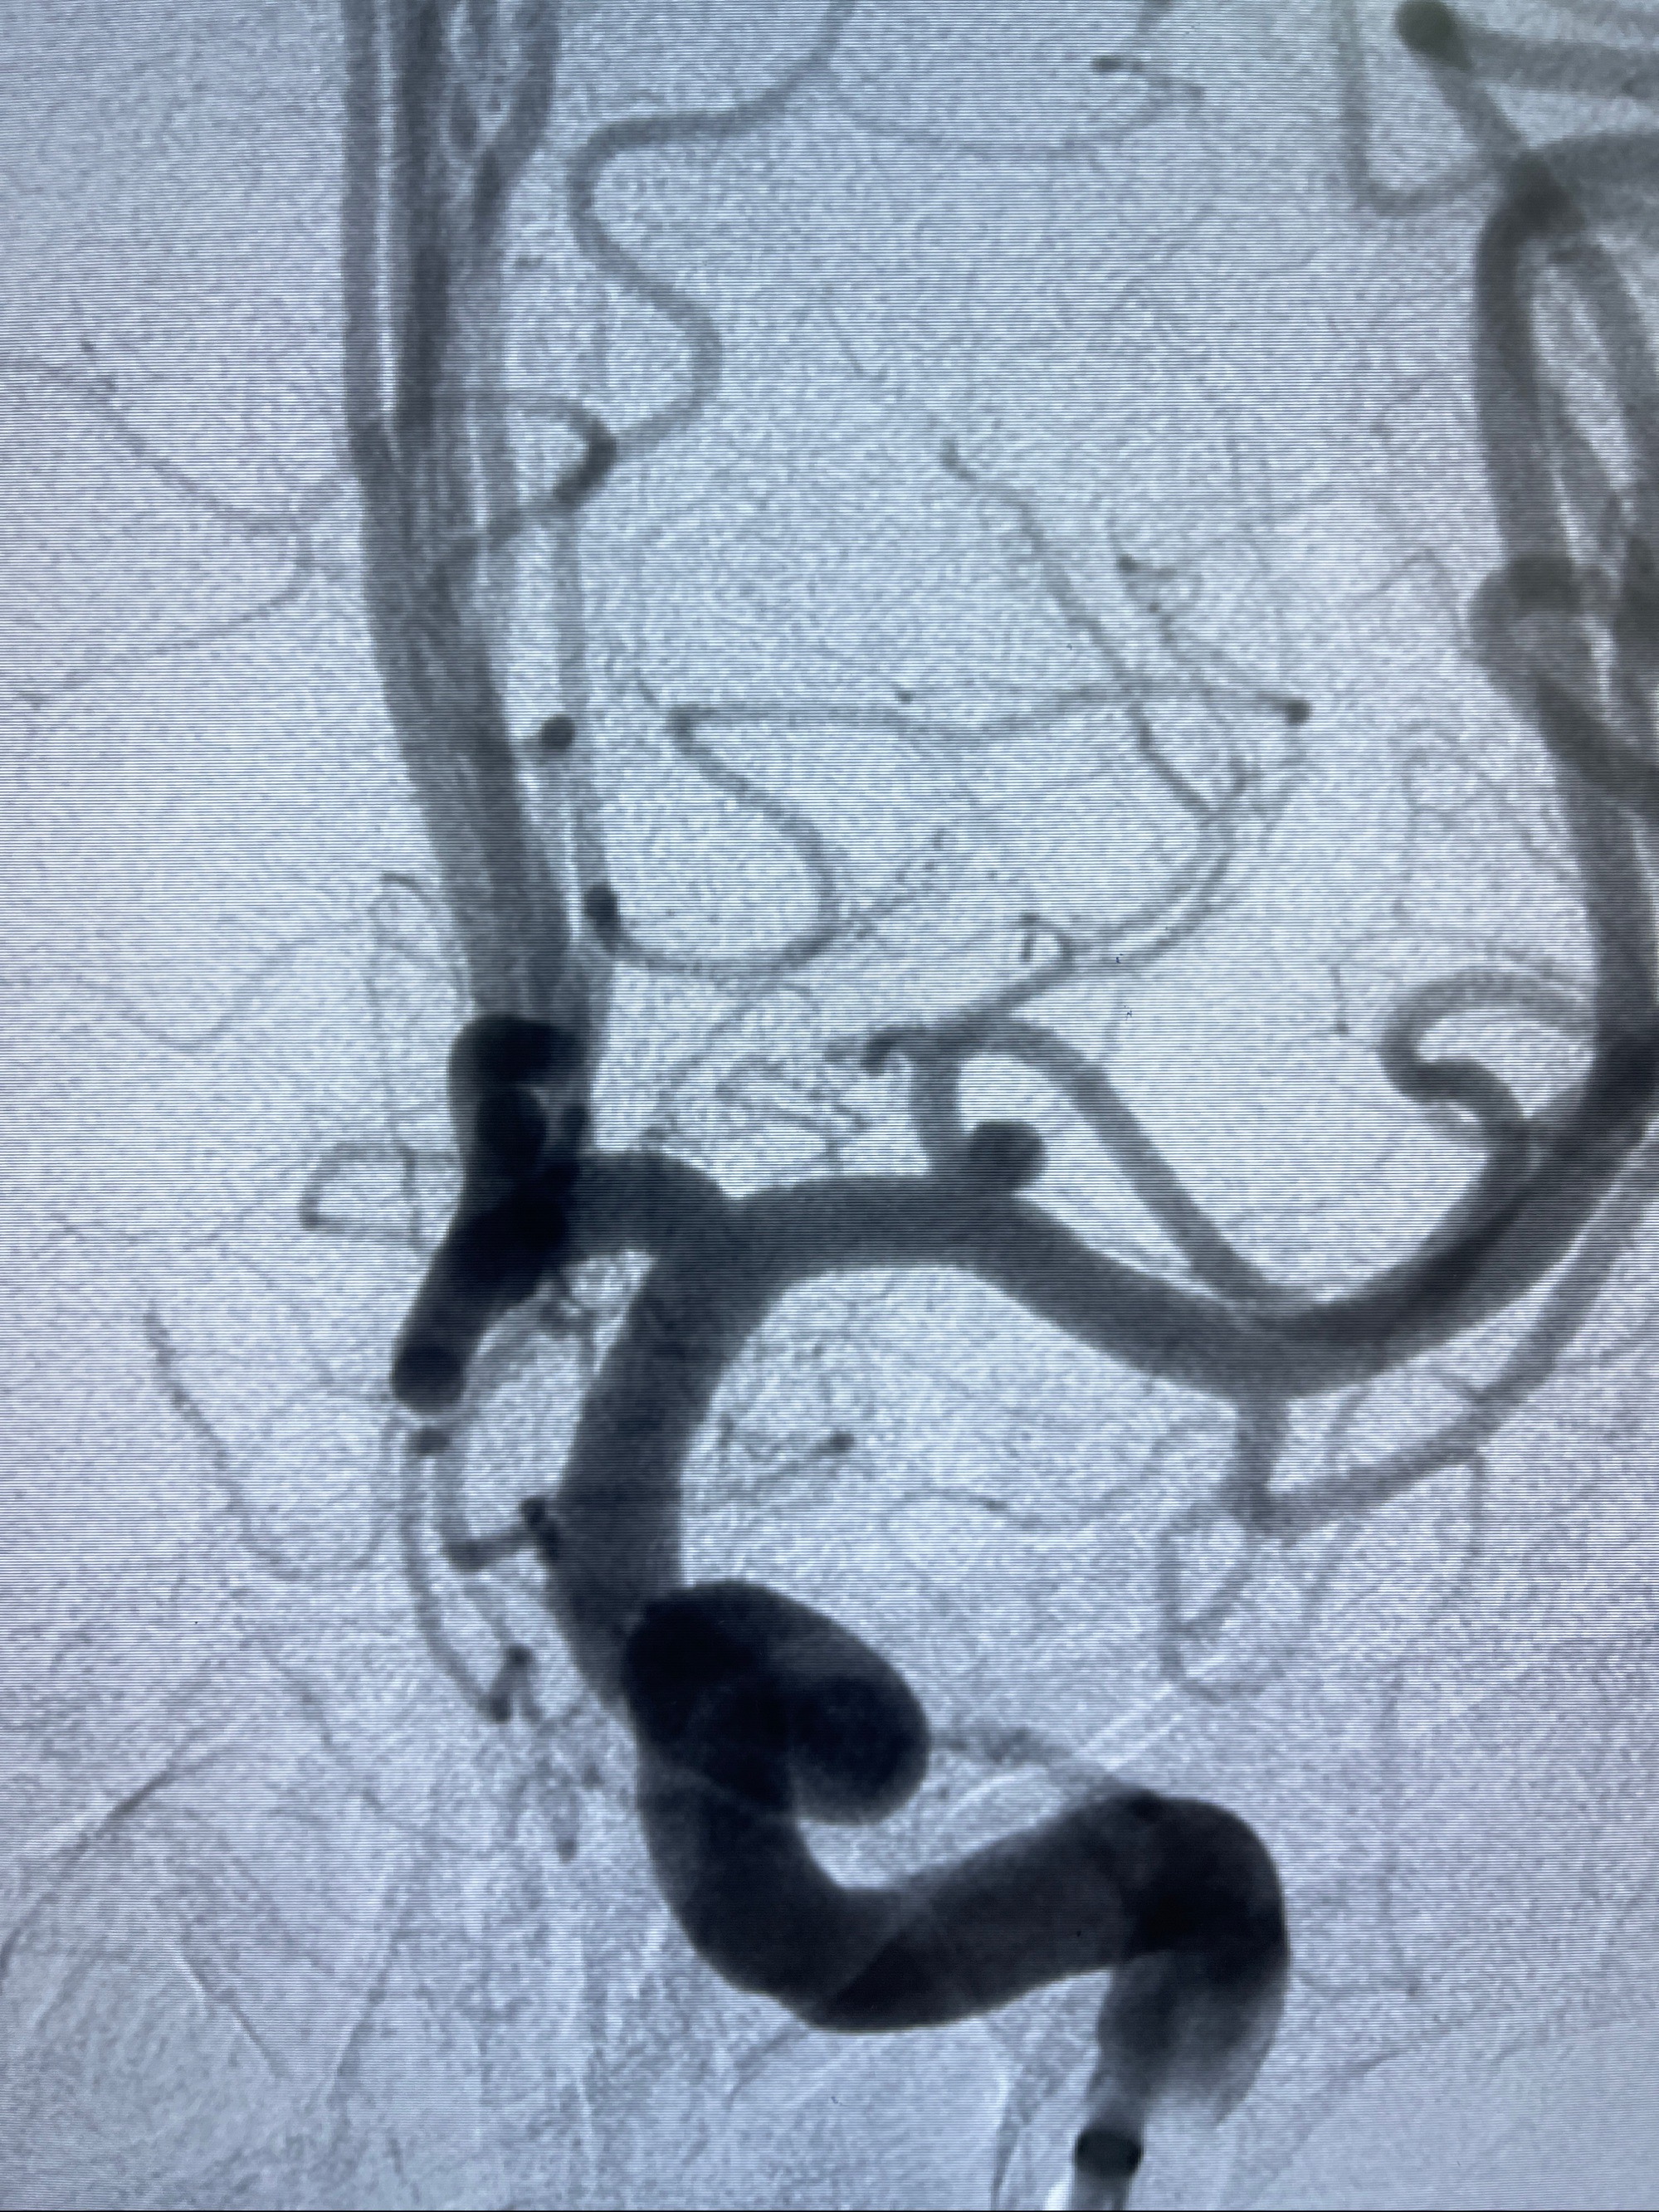

2023-08-14DSA:

左侧大脑中动脉动脉瘤,约2.6-2.8-3.4-2mm大小(瘤颈部、瘤体部、瘤高)

1.左侧大脑中动脉动脉瘤,约2.6-2.8-3.4-2mm大小(瘤颈部、瘤体部、瘤高)

2.外科手术夹闭or介入支架辅助栓塞